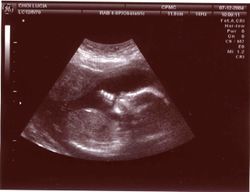

تتضمن تلك الاستعمالات التي تستخدم فيها الموجات فوق الصوتية في الحصول على المعلومات فقط. على سبيل المثال، يستخدم الأطباء الموجات فوق الصوتية للتأكد من نمو الأجنة0 ويمكن لبعض معدات الموجات فوق الصوتية رسم صورة الجنين على شاشة. كما تساعد هذه المعدات أيضاً في تشخيص الأورام وحصوات المرارة وأمراض القلب، علاوة على بعض الاضطرابات الأخرى. ويعتقد معظم الأطباء أنه لاتوجد آثار جانبية خطيرة للفحوص التي تستخدم فيها الموجات فوق الصوتية.